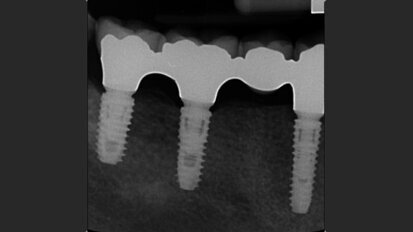

Free webinar: Expert to lecture on implant placement in the aesthetic zone

BERLIN, Germany: Some experts now believe that in order to obtain stable results in the medium and long term, the aesthetic zone should be treated in most ...